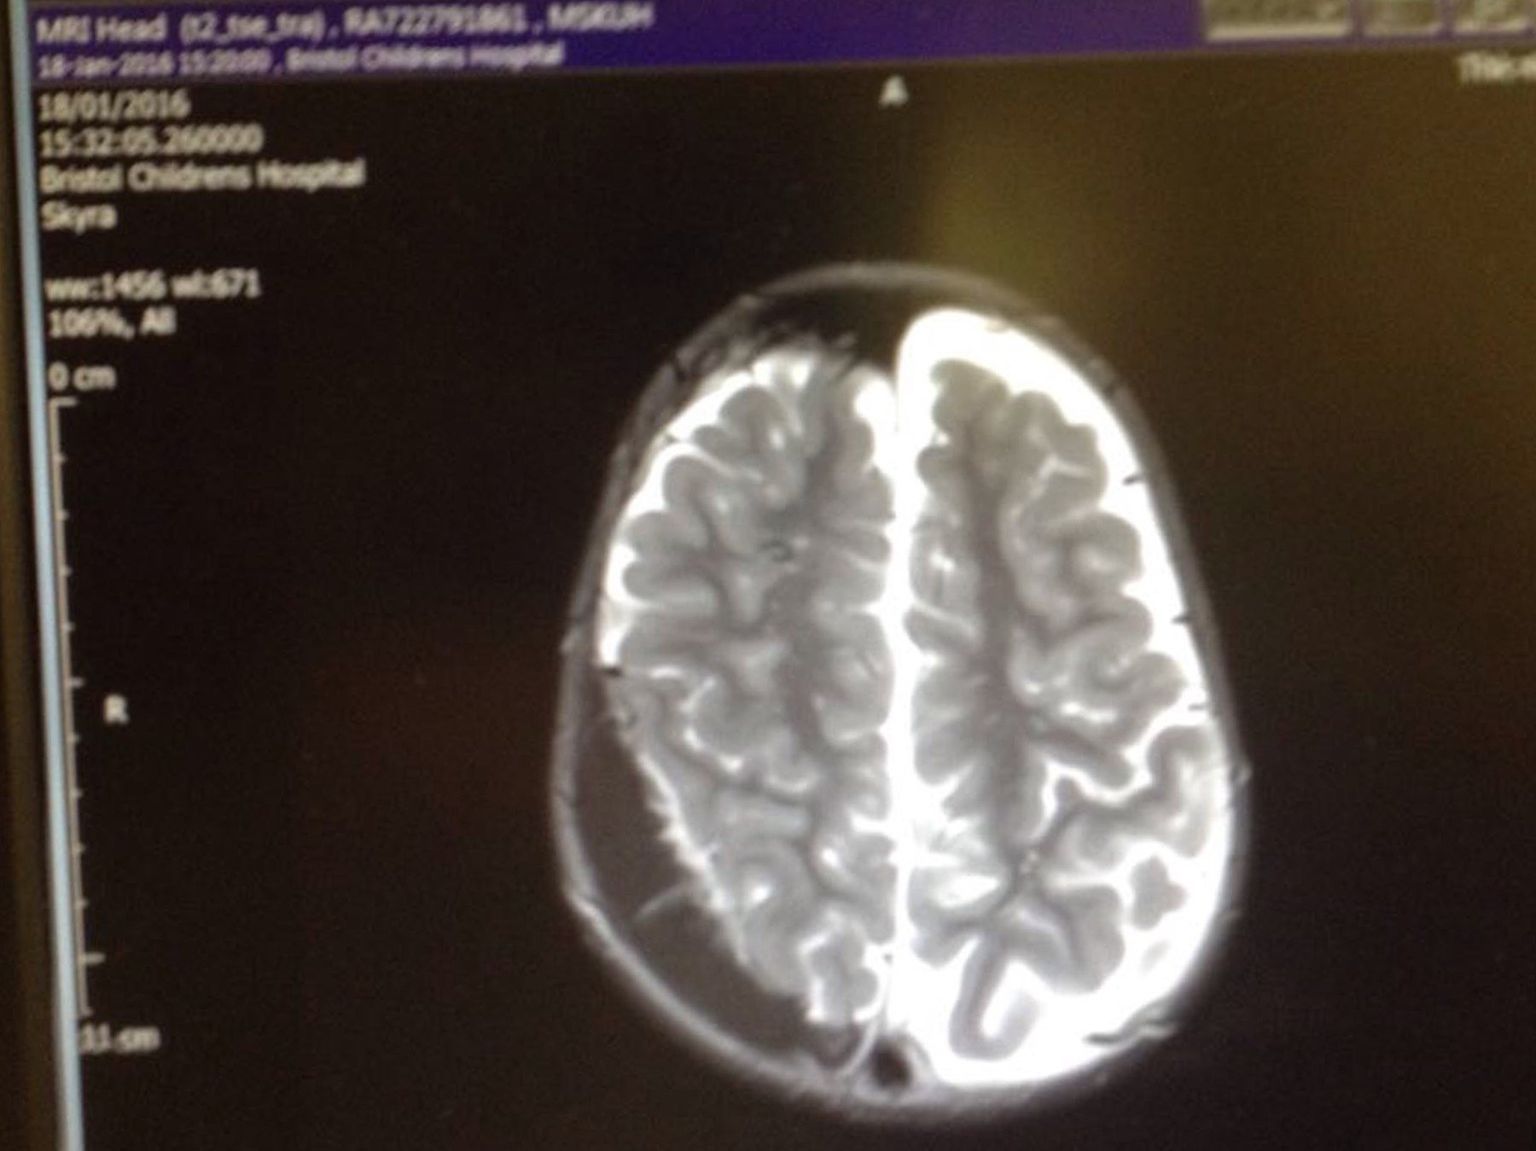

Da ti pukne srce: Ovaj hrabri trogodišnjak trpi čak 300 epileptičnih napadaja dnevno, liječnici ne daju nadu

• 3-godišnji Corey Alway boluje od dva rijetka genetska poremećaja (Foto: Profimedia) Foto: Profimedia